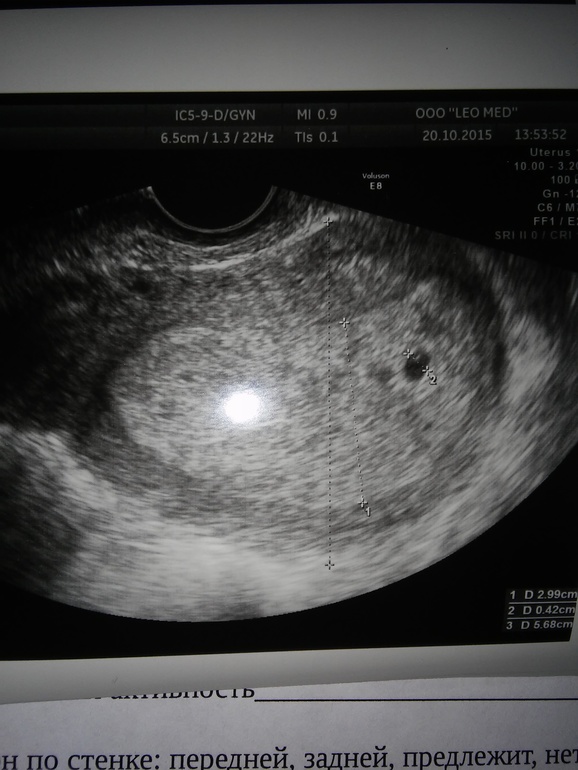

Девочки, всем привет! Диагноз вторичное бесплодие, фолликулогенез несколько циклов-ановуляция, в этом цикле-Лютеинизация неовулирующего фол. даже с уколом хгч!Сказали, что 1 шанс из 100, что что-то проскочило.Слёзы, а потом 2 полоски!Хгч больше 2000 вчера и сегодня узи

беременность 3-4 недельки!!Показали бусинку и даже подозрение на вторую рядом бусинку!!Чудеса бывают, главное верить!!Желаю как можно скорее всем испытать это счастье!!!теперь храним нашего малыша))))